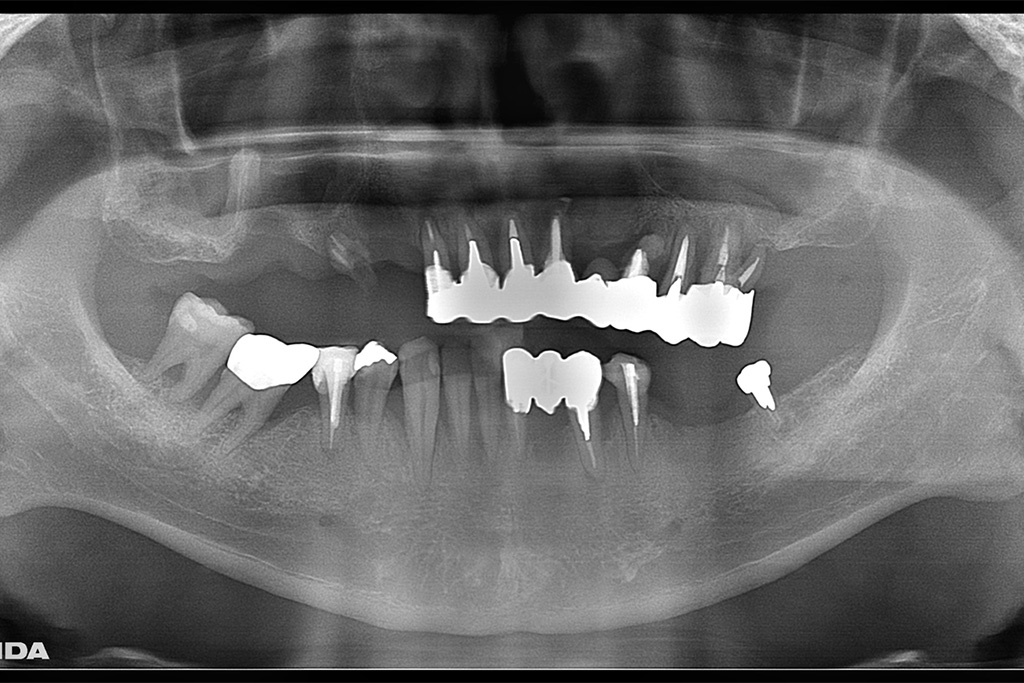

左側のレントゲンがが最初の状態です。右側がインプラントを入れ、被せ物まで入れた状態のレントゲンです。

今回は噛めることと見た目の改善を目的として上顎はダメな部分は抜歯をし、インプラントを入れました。

Hさまのインプラント治療は1年かかりました。理由としてはヘビースモーカーのためインプラントが骨と定着しなかった部分があったため何本か抜けてしまったりし、再度インプラントを入れ直したり等したためです。

タバコを止めることがストレスになるとのことでした。インプラント治療には禁煙は必須ですがストレスのが強いのであれば、インプラントが定着せず抜けてしまう可能性は増えますが、辛抱強く行えばインプラントはいつかは定着すると私も勉強させられました。